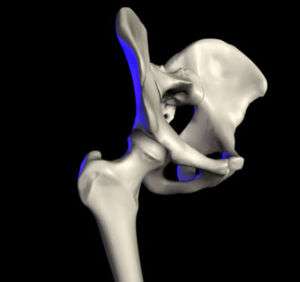

The hip joint is a synovial joint formed by the articulation of the rounded head of the femur and the cup-like acetabulum of the pelvis. It forms the primary connection between the bones of the lower limb and the axial skeleton of the trunk and pelvis. Both joint surfaces are covered with a strong but lubricated layer called articular hyaline cartilage. The cuplike acetabulum forms at the union of three pelvic bones — the ilium, pubis, and ischium.[5] The Y-shaped growth plate that separates them, the triradiate cartilage, is fused definitively at ages 14–16.[6] It is a special type of spheroidal or ball and socket joint where the roughly spherical femoral head is largely contained within the acetabulum and has an average radius of curvature of 2.5 cm.[7] The acetabulum grasps almost half the femoral ball, a grip augmented by a ring-shaped fibrocartilaginous lip, the acetabular labrum, which extends the joint beyond the equator.[5] The head of the femur is attached to the shaft by a thin neck region that is often prone to fracture in the elderly, which is mainly due to the degenerative effects of osteoporosis.

Capsule

The capsule attaches to the hip bone outside the acetabular lip which thus projects into the capsular space. On the femoral side, the distance between the head's cartilaginous rim and the capsular attachment at the base of the neck is constant, which leaves a wider extracapsular part of the neck at the back than at the front.[16] [17]

The strong but loose fibrous capsule of the hip joint permits the hip joint to have the second largest range of movement (second only to the shoulder) and yet support the weight of the body, arms and head.

The capsule has two sets of fibers: longitudinal and circular.

- The circular fibers form a collar around the femoral neck called the zona orbicularis.

- The longitudinal retinacular fibers travel along the neck and carry blood vessels.